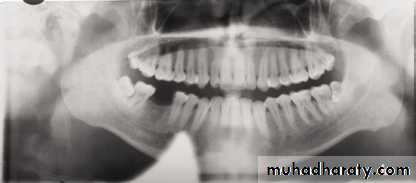

Head twisted; note uneven width of rami,

unequal magnification of teeth, and condylesHints

Slumped; note the white spine shadow in

midline1.Large anatomic area is imaged on one film , even when patient is unable to open his mouth .